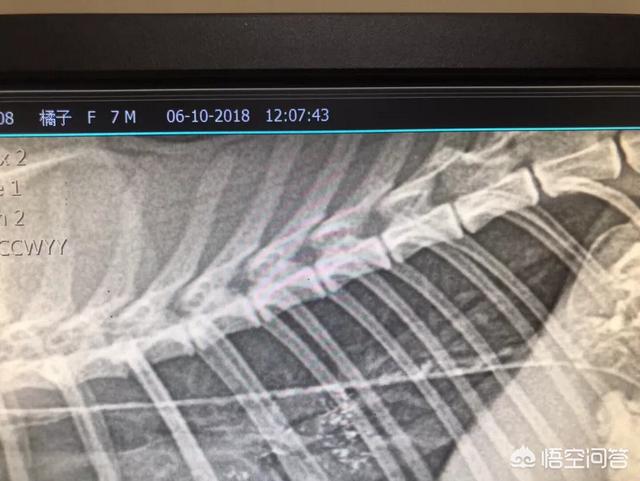

第一,猫咪绝育没有绝育之前,发情期间会出去造成咬伤甚至出现败血症等,在外部受到其他猎物追击或者挨饿受冻的的概率会急剧会增加。大家都会知道发情期间的猫咪,不管是公猫还是母的猫咪有可能就特别喜欢外出,在外面以后,可能遇到各种各样的问题。第二,猫咪做完绝育之后。对于母猫来说子宫蓄脓和乳腺肿瘤的发病率会低很多。对于子宫蓄脓,大家可能都比较熟悉,这主要是因为激素原因造成的。对于乳腺肿瘤,特别是猫咪乳腺肿瘤百分之九十以上都是属于恶性的,所以这一块需要特别的注意。

猫咪频繁发情会造成生殖系统疾病,母猫会发生卵巢、子宫和乳房病变,公猫则容易产生生殖器和尿路问题。